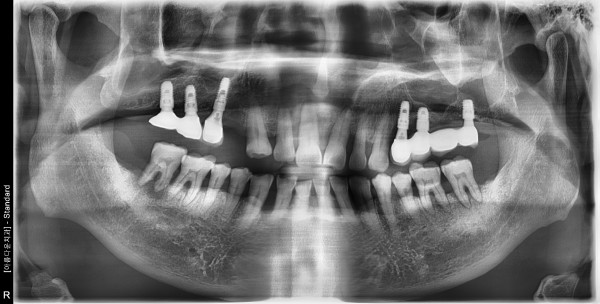

67세 남자환자 / 우측 상악 소구치 , 하악 대구치 발치 후 뼈이식 및 임플란트식립